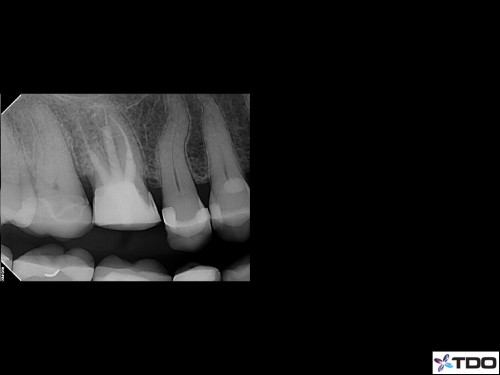

65 year-old female in good health. Root canal treatment was completed by my predecessor 15 years ago. She lost the post/crown two weeks ago. Tooth is asymptomatic. Referring doc asked if I would “do one of your magic cores so we can hold onto this tooth for a little bit longer.” No problem.

[post-views]